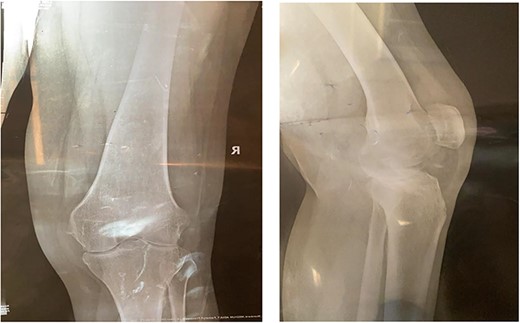

A 32-year-old female known case of rheumatoid arthritis affecting both knees presented to our clinic complaining of severe right knee stiffness post TKA 4-years-ago done in an outside facility (Figs. 1 and 2). She lives in a rural community and was on hydroxychloroquine, but her disease was active as she was not compliant to her medication. On physical examinations, the right knee was larger in size compared to the left knee without joint effusion. Range of motion was zero on flexion, −10° in extension. Standing knee X-ray showed HO around the prosthesis (Fig. 2). Computed tomography (CT) demonstrated extensive HO with implants fixed in place (Fig. 3). Revision surgery and replacement of the prostheses was considered to restore function.

Preoperative standing X-ray showing heterotopic ossification around the prosthesis with preserved knee joint. (A) Heterotopic bone extending proximally on the anterior surface of the femur. (B) Posterior heterotopic bone fusing the knee joint. Careful removal with osteotomes and bone curettes was necessary to remove the old implants.